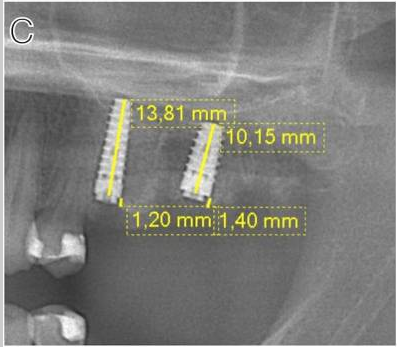

Crestal implant: (A) baseline (B) three months after placement (C) three months after loading

Subcrestal implant: (A) baseline (B) three months after placement (C) three months after loading